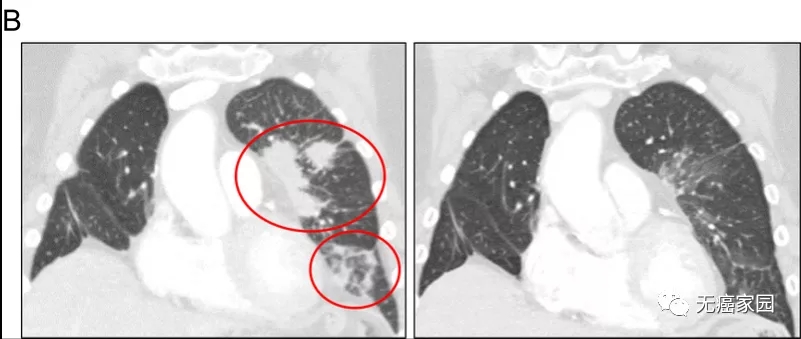

患者1对奥希替尼和BLU-667的治疗反应。胸部连续冠状对比增强计算机断层扫描图像显示,在用BLU-667和奥希替尼(右)治疗8周后,基线(左)看到右下叶肺肿块和胸膜结节(红色箭头),部分反应。

患者2对奥希替尼和BLU-667的治疗反应,与基线(左)相比,左上叶和左下叶肺混浊(右;圈出)有显著改善。